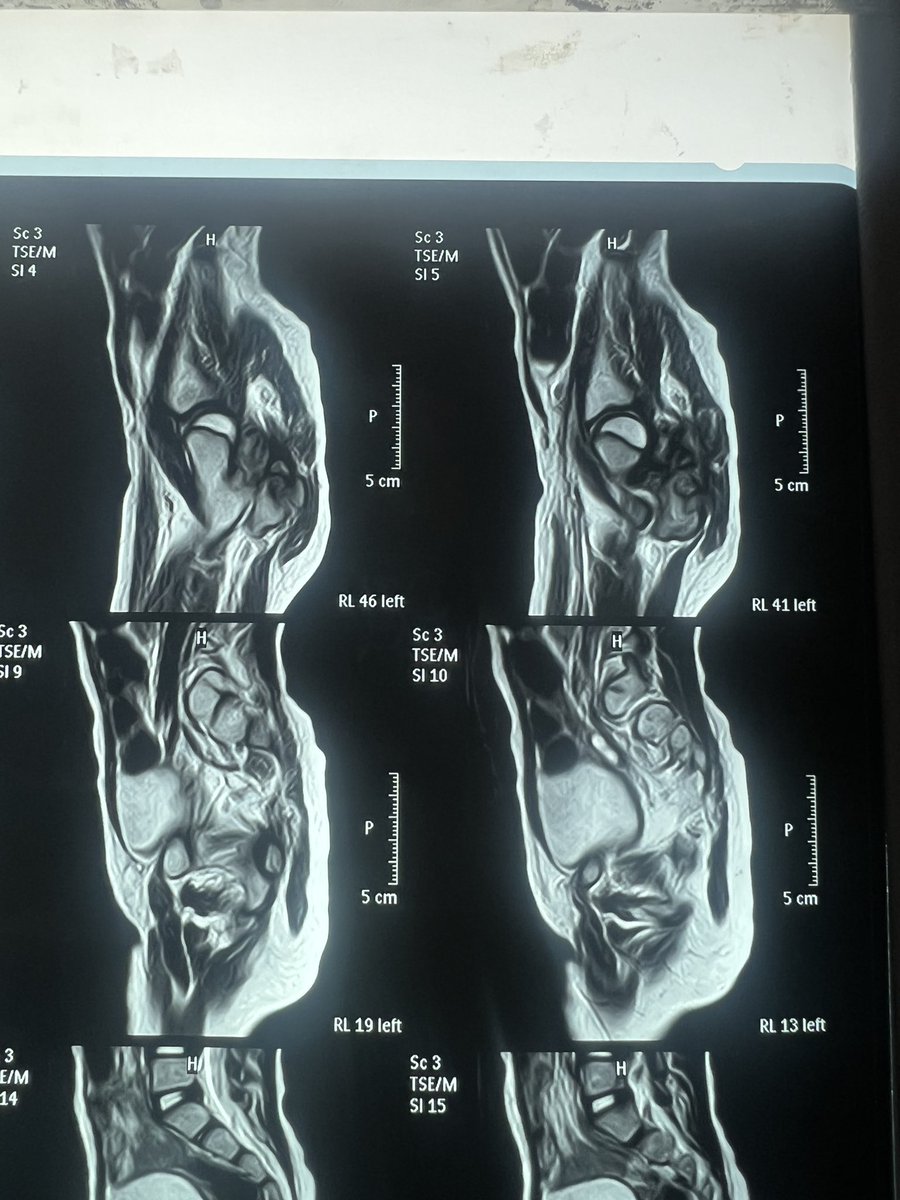

بالأمس كانت امسية ثقيلة، طفلة تعاني منذ ٥ سنوات بورم حميد نشط بمنطقة المقعدة و اسفل الحوض، و ضاغط علي العصب الوركي، و نظرا لخطورة الحالة، شرحت للاسرة احتمال اصابة العصب او قطع العصب في حالة ان العصب جزء من الورم

سنين و الطفلة تعاني من الألم.

ضعف بالرجل و اعوجاج نتيجة الالم، للأسف كان البعض ينظر لعوجة الرجل و لا ينظر الي سبب ضعف العصب و الالم.

انعم الله علينا و عليها بإستئصال الورم و الحفاظ علي العصب، و مع تسليك العصب من الورم و أستئصال الورم من الاوتار و العضلات و العظم